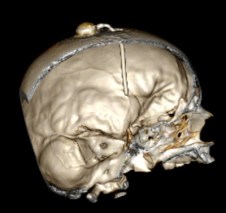

syndrome de Gorlin découvert tardivement ; noter les calcifications de la faux -